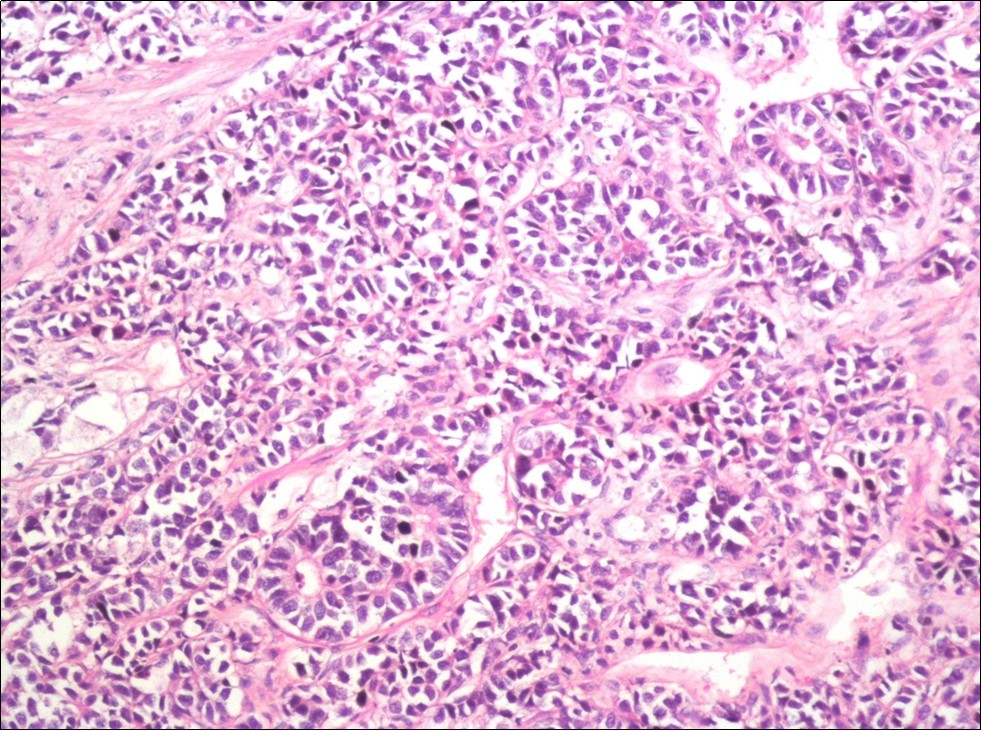

A 73-year-old male patient was admitted to our outpatient clinic with acute urinary retention. Digital rectal examination was normal. The PSA value was 1.81 ng/dl. Prostate size was 101 cc. Since the PSA value and digital rectal examination were normal, no biopsy was taken. Ultrasonography showed bilaterally ureterohydronephrosis. The creatinine level was 2.89 mg/dl. Hypertension has been presented as a comorbidity. An 18 Fr Foley catheter was inserted and alpha-blockers and 5-α reductase inhibitor medication was given. Creatinine level decreased to 0.91 mg/dl after one week. When the patient's catheter was pulled out, he could not urinate again. A catheter was inserted and waited one week more. After one week, the patient was unable to urinate again. The operation was decided due to this recurrent urinary retention. Because of prostate size was 101 cc and prostatic urethra was long, open prostatectomy was decided. When the prostate was removed during the operation, it was evaluated that the left side and the lower side were adhered to surrounding tissue. The prostate was removed as an en bloc. The catheter was removed after 5 days. The pathology of the patient has been reported as pure small cell prostate carcinoma. On the microscopic examination, the tumor was heavily infiltrated into the prostate parenchyma (Figure 1). Tumor cells were consist of atypical small-medium sized, mitotically active cells with a high nuclear to cytoplasmic ratio, hyperchromatic nucleus, nuclear molding, and inconspicuous nucleoli (Figure 2). On the immunohistochemically examination of synaptophysin showed diffusely and strong positivity while chromogranin A showed focal weak positivity with the absence of staining for PSA (Figure 3). Ki67 proliferative index was equal to 90% of the tumor cells (Figure 4). The results confirmed the diagnosis of prostatic small cell carcinoma. Metastatic lymph nodes were detected in the right perirectal region with metastatic multiple lymph nodes in the bilateral external iliac region, more on the left than in the PET CT. No metastasis was detected in the brain MRI and thorax computed tomography. Four cycles of etoposide and cisplatin chemotherapy were administered to the patient. Control PET CT taken after chemotherapy showed a significant decrease in size and metabolic activity of the right obturator and lymph nodes in the right perirectal area. The size and metabolic character of the left obturator, left external iliac and common iliac lymph nodes were increased. After a month, patient admitted to emergency outpatient clinic with left flank pain. There was an 8-cm mass in retroperitoneal area in the computed tomography. Supportive treatment was started because the patient could not tolerate chemotherapy. The masses reached to 13x11cm and fulfilled the retroperitoneal area. Multiple lung metastases were seen. The patient died 13 months later after the first diagnosis.

Figure 3.Diffusely and strong immunostaining for synaptophysin (Synaptophysin, x200)